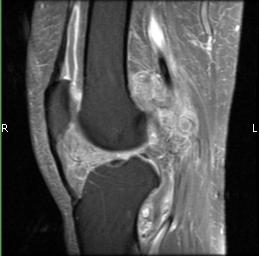

Radiographic imaging is used to help form a diagnosis of PVNS. These include X-Ray, MRI, CT and Bone Scans

An example of an MRI is shown.

MRI PVNS